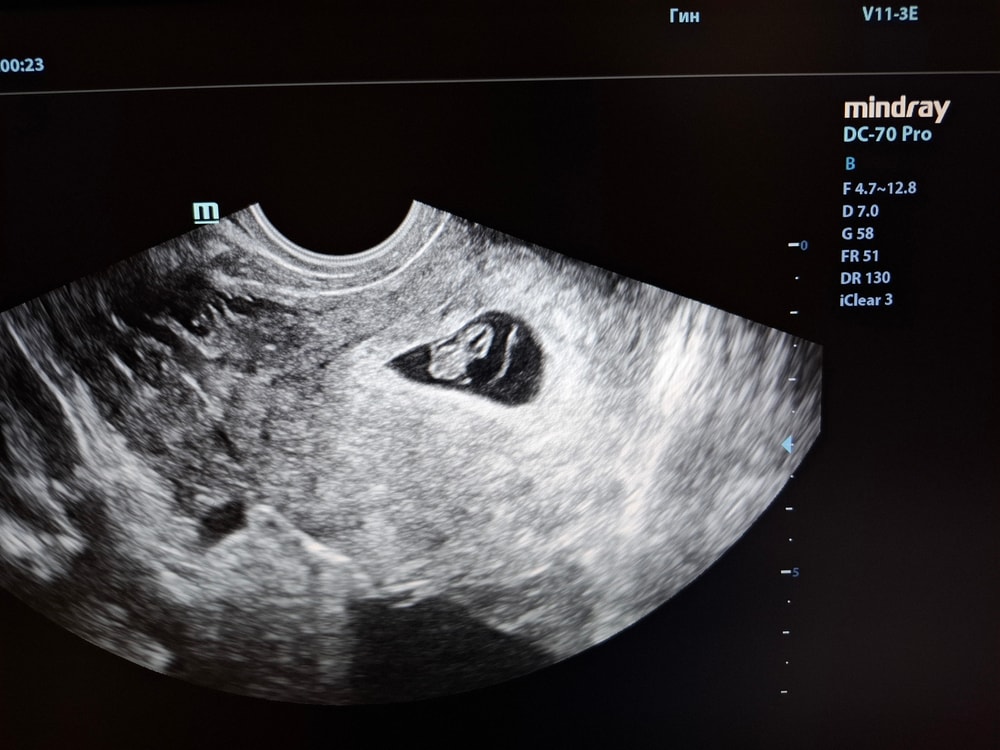

Узи 36 дпп

Результаты УЗИВот и сходила я на узи.

Пя 28 мм ( на 28 дпп было 23 мм)

Жм 5 мм ( на 28 дпп был 4 мм)

Ктр 10 мм ( нп 28 дпп был 7 мм)

Сердцебиение 130 уд/мин

Хорион по передней стенке

Киста уменьшилась и стала 43×29 мм. ( на 28 дпп была 70×70мм)

Поставили срок 7 недель. Сейчас по месячным 8,4 недели ( подсадка была 5 дневки на 25 дц).

Моя крошечка🥰🥰 мне кажется маловато конечно подросли,но списываю на погрешность измерения и другой аппарат узи. Сколько у вас был ктр на 35-36 дпп?